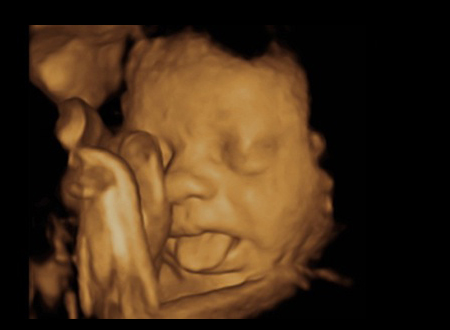

Nu mereu reușești să surprinzi atât de bine anumite imagini de ecograf. Tocmai de aceea, imaginile prezentate sunt foarte RARE!